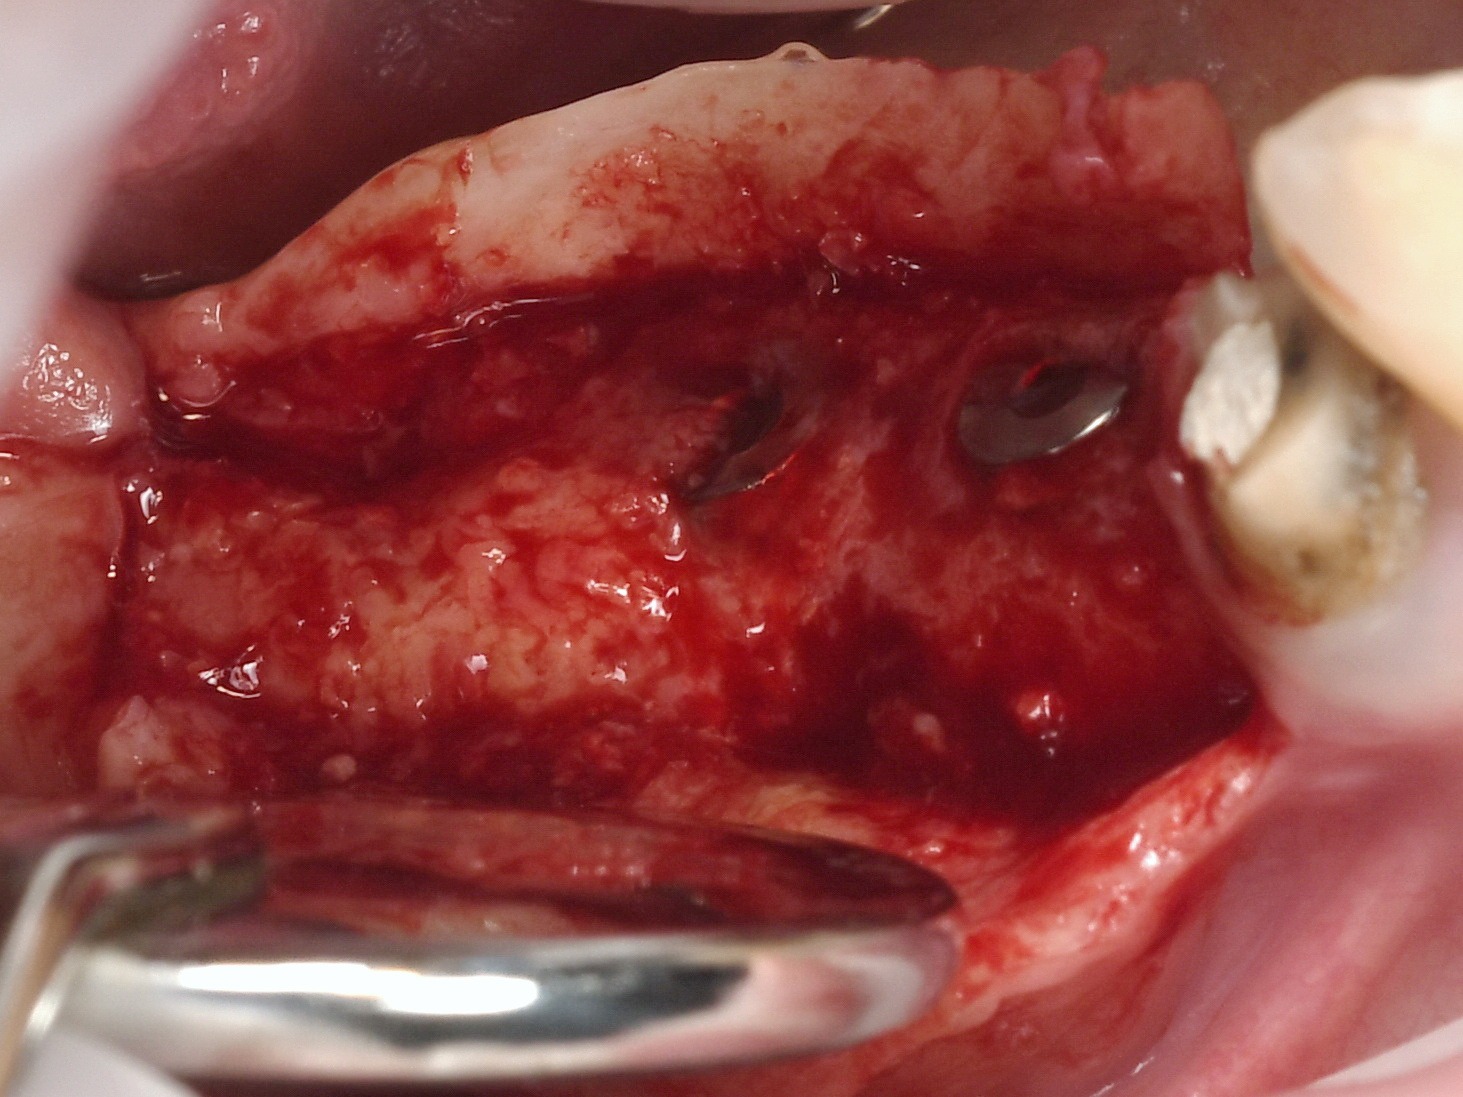

Lateral ridge augmentation with simultaneous implant placement